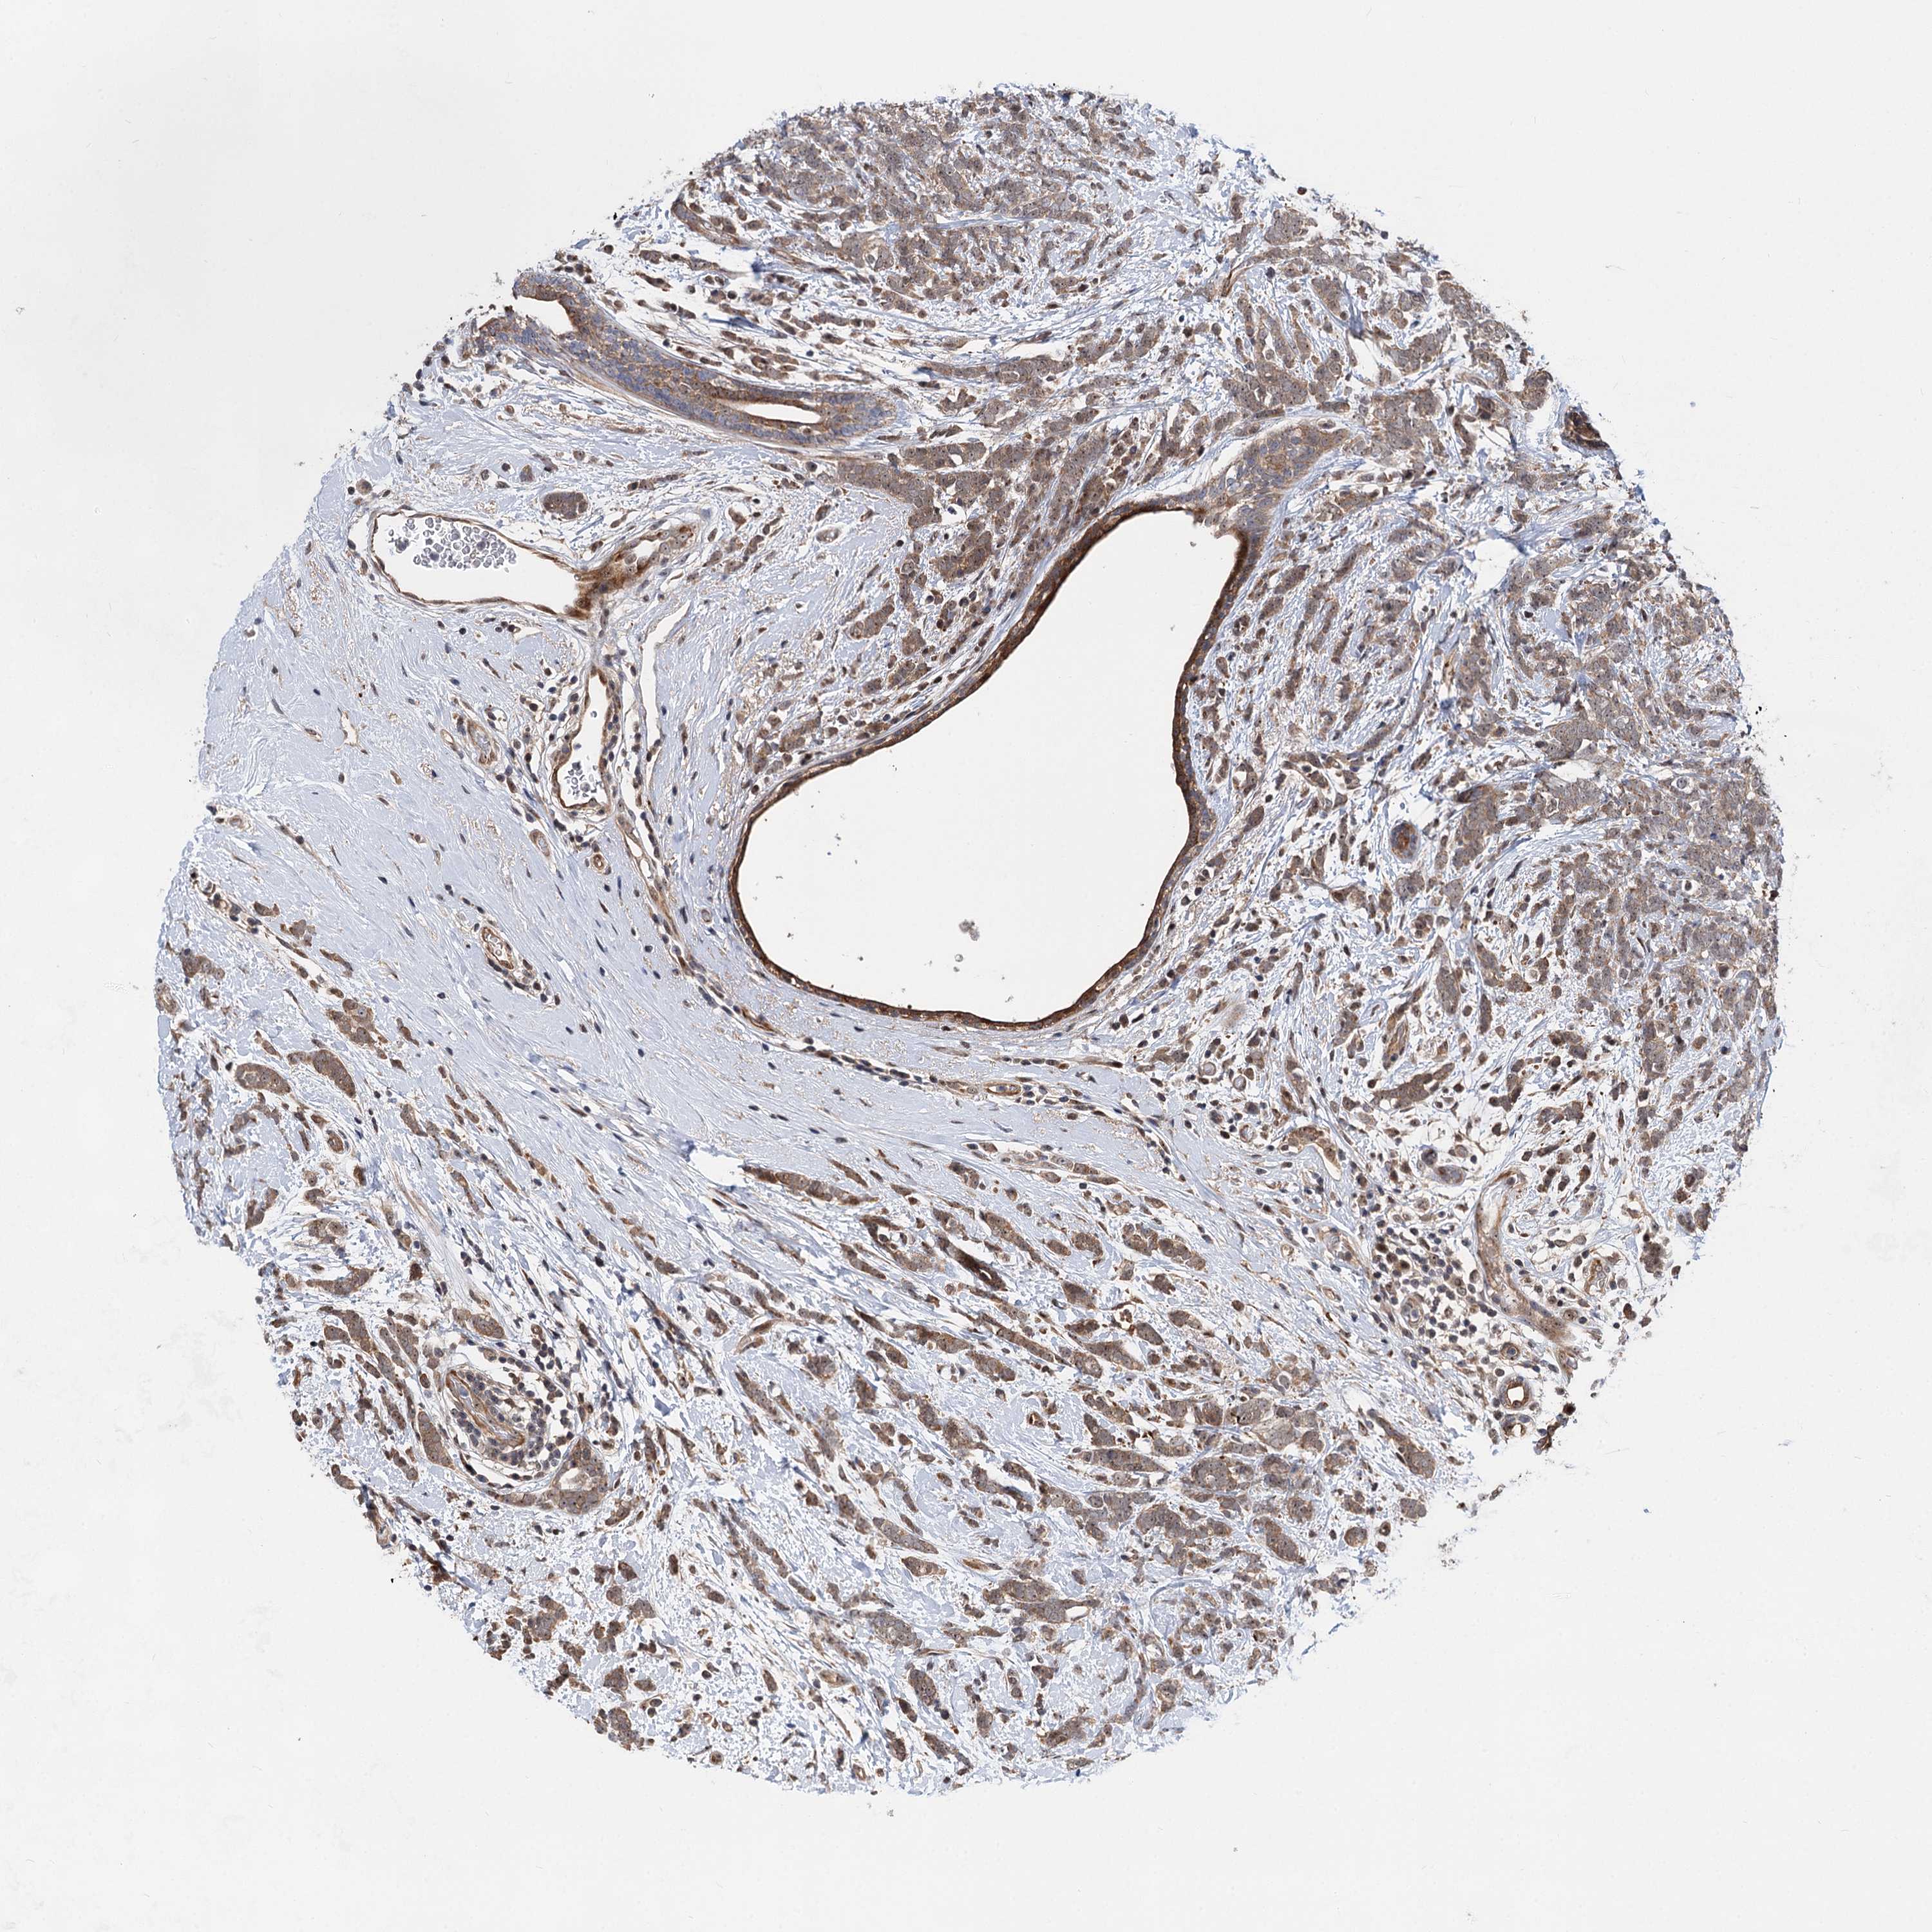

CANCER BREAST CANCER Show tissue menu

BRCA TCGA BRCA VALIDATION PROTEIN EXPRESSION

Breast cancer

Human cancer

Breast invasive carcinoma